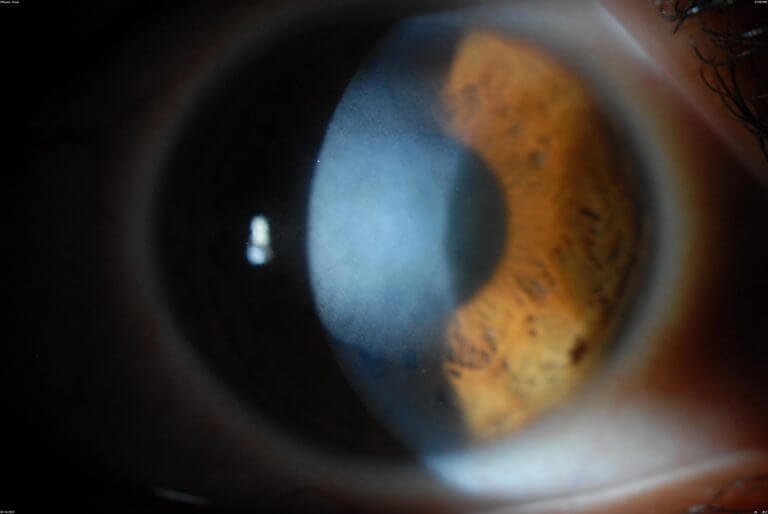

Corneal vascularization and scarring American Academy of Ophthalmology Can Corneal Scars Be Removed corneal scarring can impair your vision and cause pain. Learn about the causes, symptoms and treatment options for. — surgical interventions for corneal scarring may include procedures such as phototherapeutic keratectomy. — during transplant surgery, either the whole cornea or portions of the cornea are removed and replaced with donor human cornea. — management of the. Can Corneal Scars Be Removed.